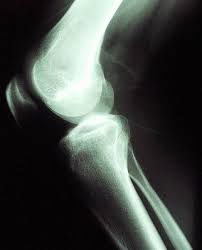

Segundo os autos, M.L.N. foi diagnosticada com artrose e o médico indicou cirurgia no joelho direito para implantação de prótese. O plano de saúde, no entanto, negou o pedido, sob a justificativa de que o contrato não cobria o procedimento.